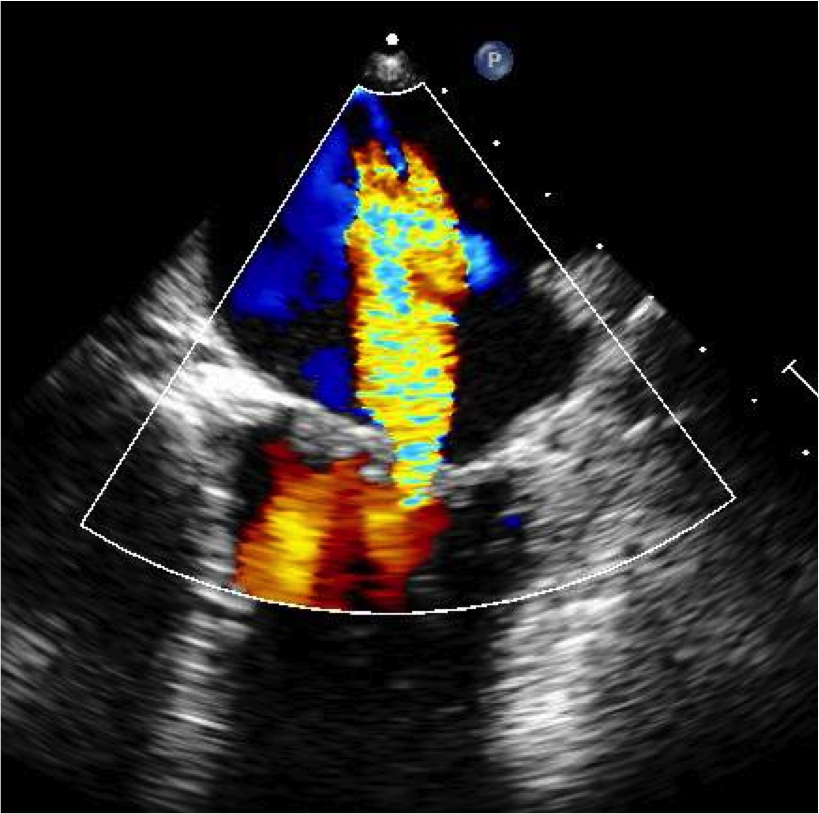

Transesophageal Echocardiogram Mitral Regurgitation

Echo showing mitral regurgitation

A transthoracic echocardiogram "echo" is a non-invasive test that uses sound waves bouncing off the heart structures to see inside the heart.  It also uses doppler imaging (like the weather imaging you see) to "see" the abnormal blood flow caused by a diseased valve.  For instance, you can actually see the blood flowing backwards in mitral regurgitation. A transesophageal echocardiogram (TEE) may be required to better view the valve.  This procedure involves sedation similar to a colonoscopy (but no bowel prep) and takes advantage of the fact that the esophagus (swallowing tube) sits right behind the left atrium of the heart.  There are some risks with TEE but they occur with a low incidence (such as perforation of the esophagus or complications of sedation).  The other benefit of a well-done echocardiogram is that it can help the surgeon predict if the valve will be easy or difficult to repair and can give the patient and their family an estimate of how likely repair is versus replacement.  We find 3D TEE to be particularly helpful in planning out the repair strategy prior to surgery which we believe increases the repair rate.